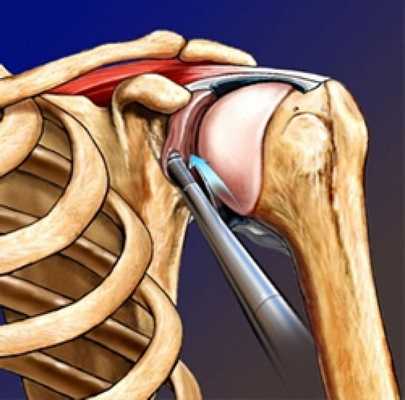

Артроскопия плеча - малоинвазивное хирургическое вмешательство, при котором через несколько проколов внутрь сустава и подакромиальное пространство вводится оптика, освещение, хирургический инструментарий. Все манипуляции проводятся под контролем видеокамеры. Врач отслеживает изображение на экране и использует инструменты с помощью манипуляторов.

Положение тела пациента - «пляжное кресло». Для доступа делаются три небольших разреза. Определяется с помощью введенного в сустав артроскопа расположение поврежденной суставной губы. Она фиксируется. Проводится и фиксация суставной капсулы. Оценивается размер повреждения костной части гленоида. Устанавливаются якорные фиксаторы - от 3 до 5 штук, исходя из обширности повреждения.

Артроскопия позволяет диагностировать повреждения сустава изнутри, С помощью манипуляторов из суставной капсулы формируют новую суставную губу, которую фиксируют на кости при помощи специальных якорных фиксаторов. Якорные фиксаторы представляют собой специальные приспособления с прочными нитями и фиксатором, расположенным на одном конце. Они могут быть изготовлены из металла или рассасывающихся материалов.